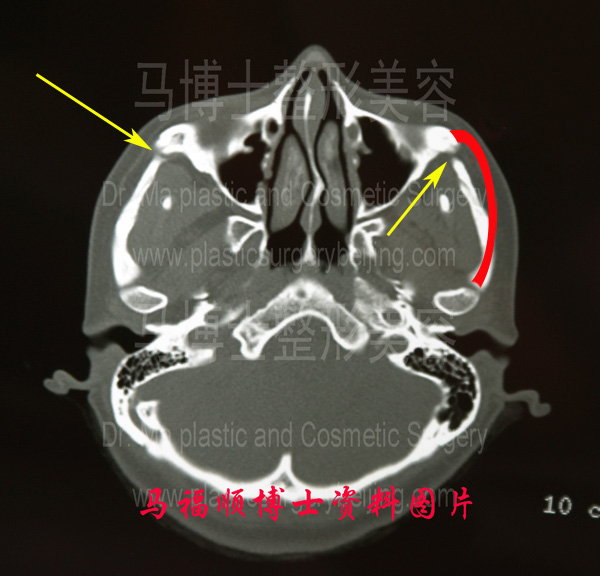

黄色箭头示颧弓骨已经不再连续,断端之间还有一定的距离,这样不利于骨骼愈合。红色箭头表示前端内收,但后端的宽度没有变化。

上图为颧骨颧弓前端截骨整形术后的CT断层照片。左侧图示中黄色箭头所示的颧骨颧弓前端已经被切开,由于切开的位置切除了一段骨骼,所以骨骼切口的两端不能完全对合,黄色箭头示骨骼的两侧断端之间有间隙,这样骨骼愈合受到影响,使颧骨颧弓的强度变弱。

右侧图片中红色单箭头示颧骨颧弓的前端向内推移,红色弧线表示手术前颧弓的形状及位置,与手术前相比颧骨颧弓前端有明显内收,但后端相当于红色双头箭头处,是颧弓内推时的转动轴心点,这一位置的宽度在前端内推后并没有变化,这样就会显的面部耳前的位置,也就是术前颧弓的最高点更加突出,造成一种术后从正面观察时脸变得更宽的感觉。